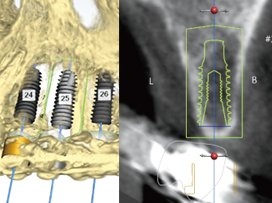

3D Diagnosis via CT Scan

Using 3D data from CT imaging and dental models, we perform a comprehensive and precise diagnosis that considers bone, gingiva, and nerve anatomy.

Computer-Based Surgical Planning

We perform a virtual simulation surgery on the computer to determine the precise placement position, then fabricate a custom surgical guide for accurate execution.